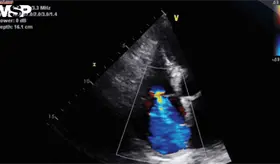

El menor un peso al nacer de 1,365 g, desarrolló síndrome de distrés respiratorio agudo en su primer día de vida, por lo que requirió soporte ventilatorio invasivo.